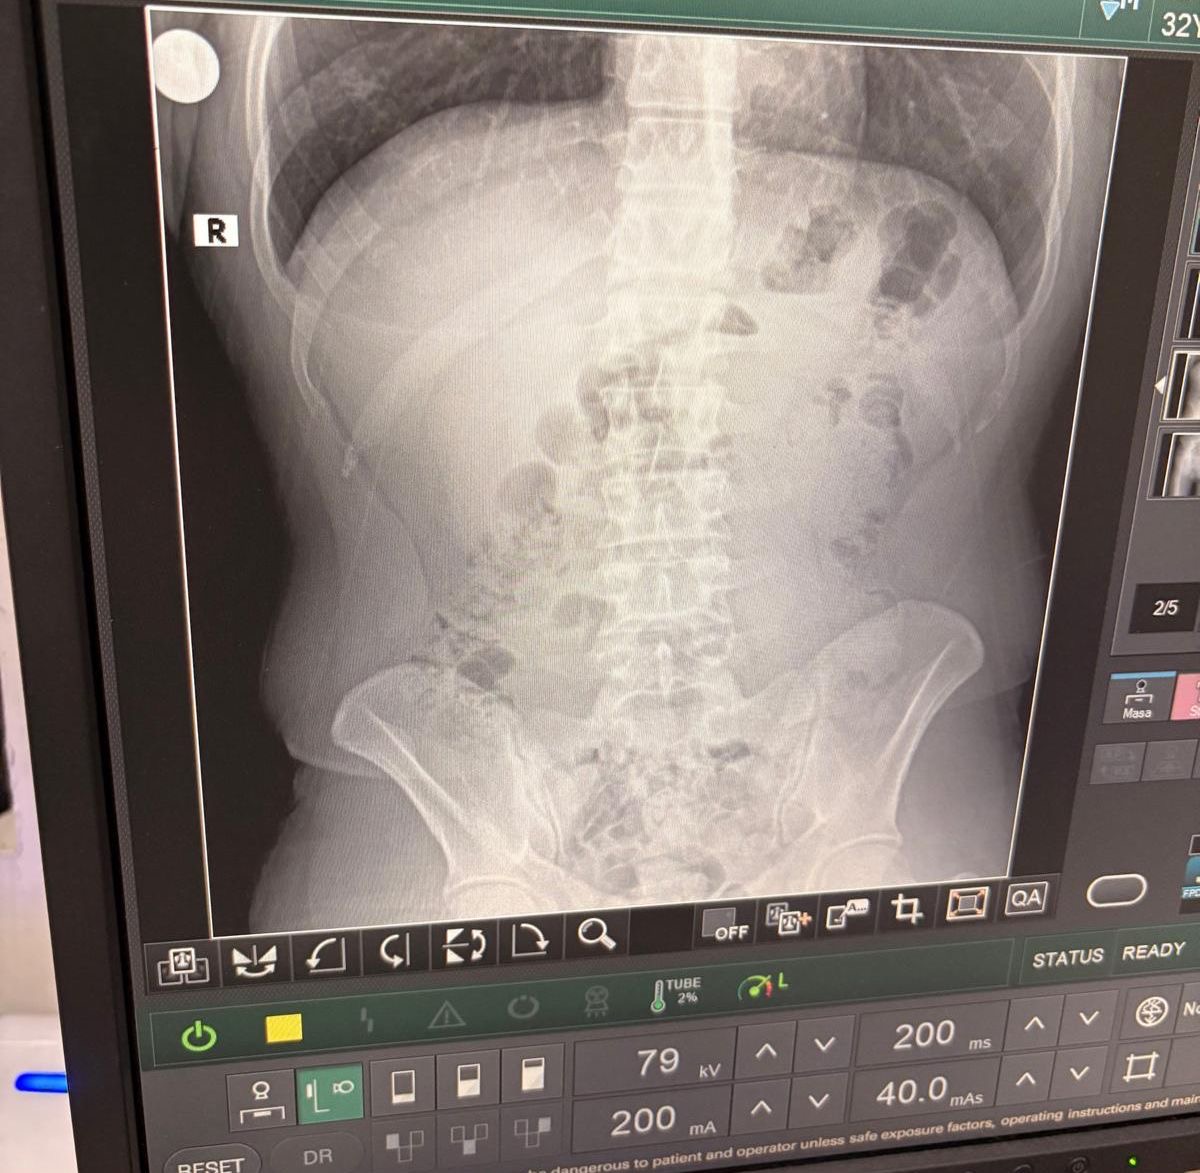

Hastanede yapılan detaylı tetkikler ve çekilen röntgen filmleri sonucunda, şüphelilerin mide ve bağırsaklarında çok sayıda kapsül bulunduğu tespit edildi. Uzman doktorlar eşliğinde gerçekleştirilen tıbbi müdahale neticesinde, toplamda 140 kapsül içinde 1 kilo 516 gram metamfetamin maddesi çıkarıldı.